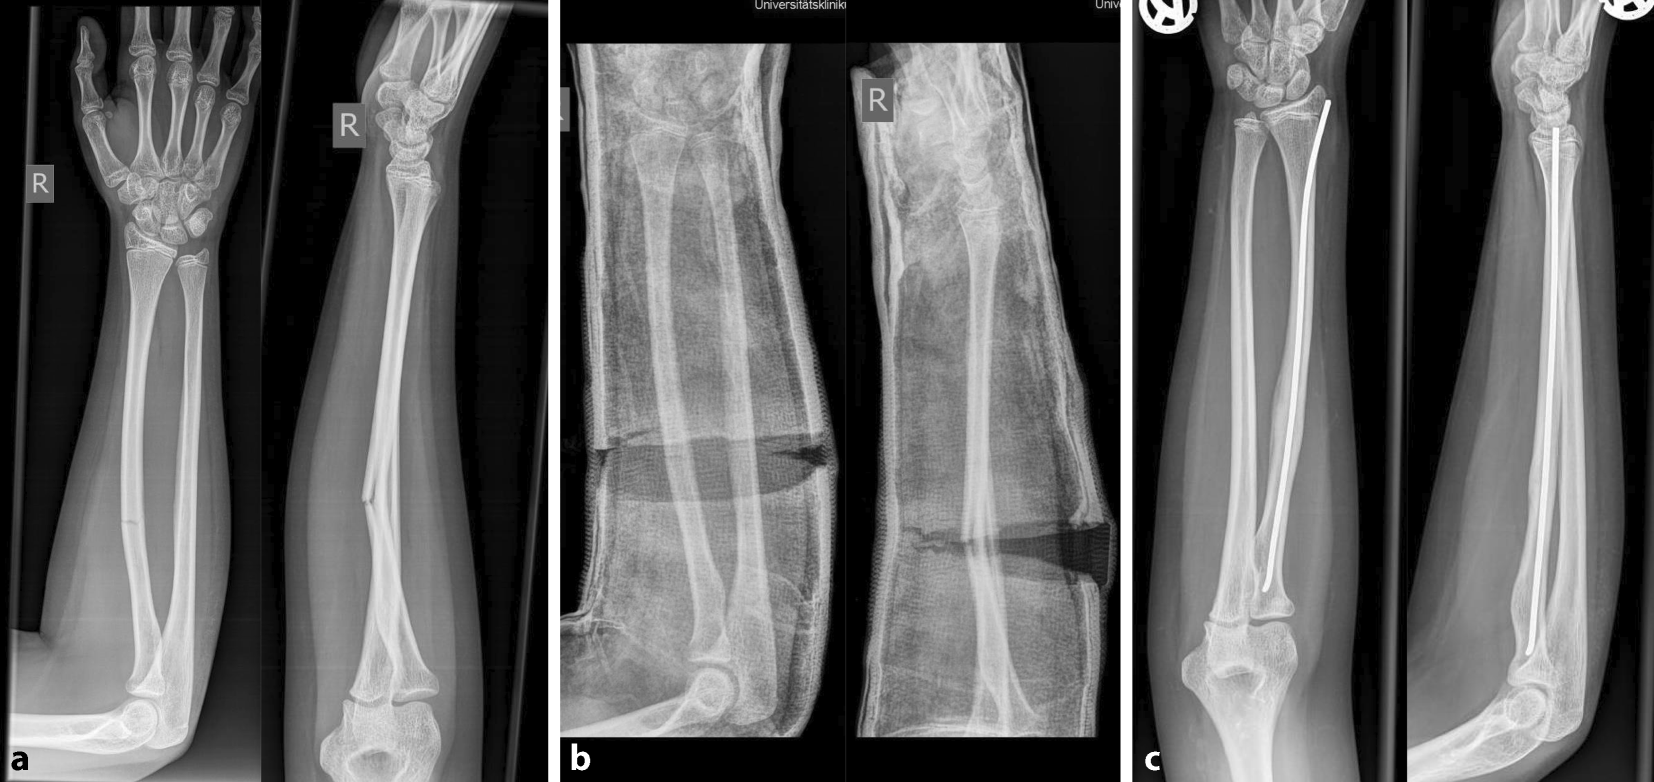

Abb. 3

Durchführung der Gipskeilung am Unterschenkel. Knabe, 11 Jahre, Sturz beim Skifahren. Tibiaspiralfraktur Übergang mittleres in distales Schaftdrittel mit Grünholzkomponente an der Fibula. Am 8. Tag nach Trauma erfolgt eine radiologische Stellungskontrolle, bei der sich eine Dislokation in den Varus und eine Retrokurvationsstellung zeigen. Zunächst Analyse der Keilungsrichtung, die Wirkung des Keils muss in der maximalen Konkavität der Frakturfehlstellung(en) zum Tragen kommen. Zur Korrektur eines isolierten Varus erfolgt die Keilung von medial (a), die Beseitigung einer alleinigen Retrokurvation gelingt durch Keilung von ventral (b). Deshalb wird im angeführten Fall die Stellungskorrektur durch Aufdehnen des Gipsverbandes von ventromedial geplant (c)

Abb. 4

Als nächster Schritt wird die Höhe des Keils bestimmt, die bei diaphysären Quer- und kurzen Schrägfrakturen direkt über dem Bruch und bei längeren Spiralfrakturen am proximalen Bruchende liegt. Im distal metaphysären Bereich Positionierung des Keils rund eine Handbreite proximal der Fraktur. Da die genaue Lokalisation mitentscheidend für das Gelingen des Keilens ist, sollte, zumindest bei anspruchsvollen Keilungen (oder beim Ungeübten), die Bestimmung der Keilungshöhe unter Bildwandlerkontrolle erfolgen. ab Keilungshöhe am proximalen Frakturende